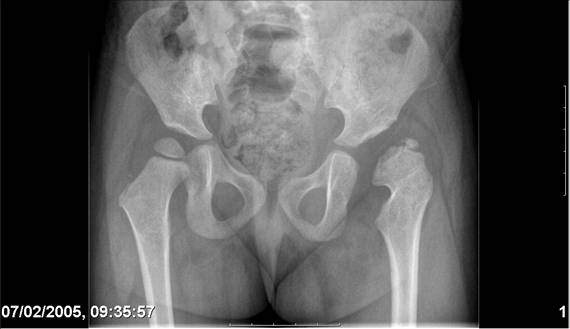

Chto by ne byt goloslovnym posilau vam svoi sluchai gde sdelal vse chto napisal vyshe